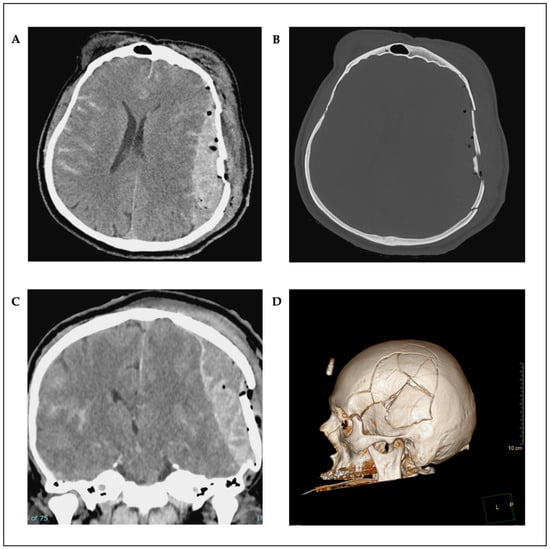

2. Case Presentation

Surgical Technique